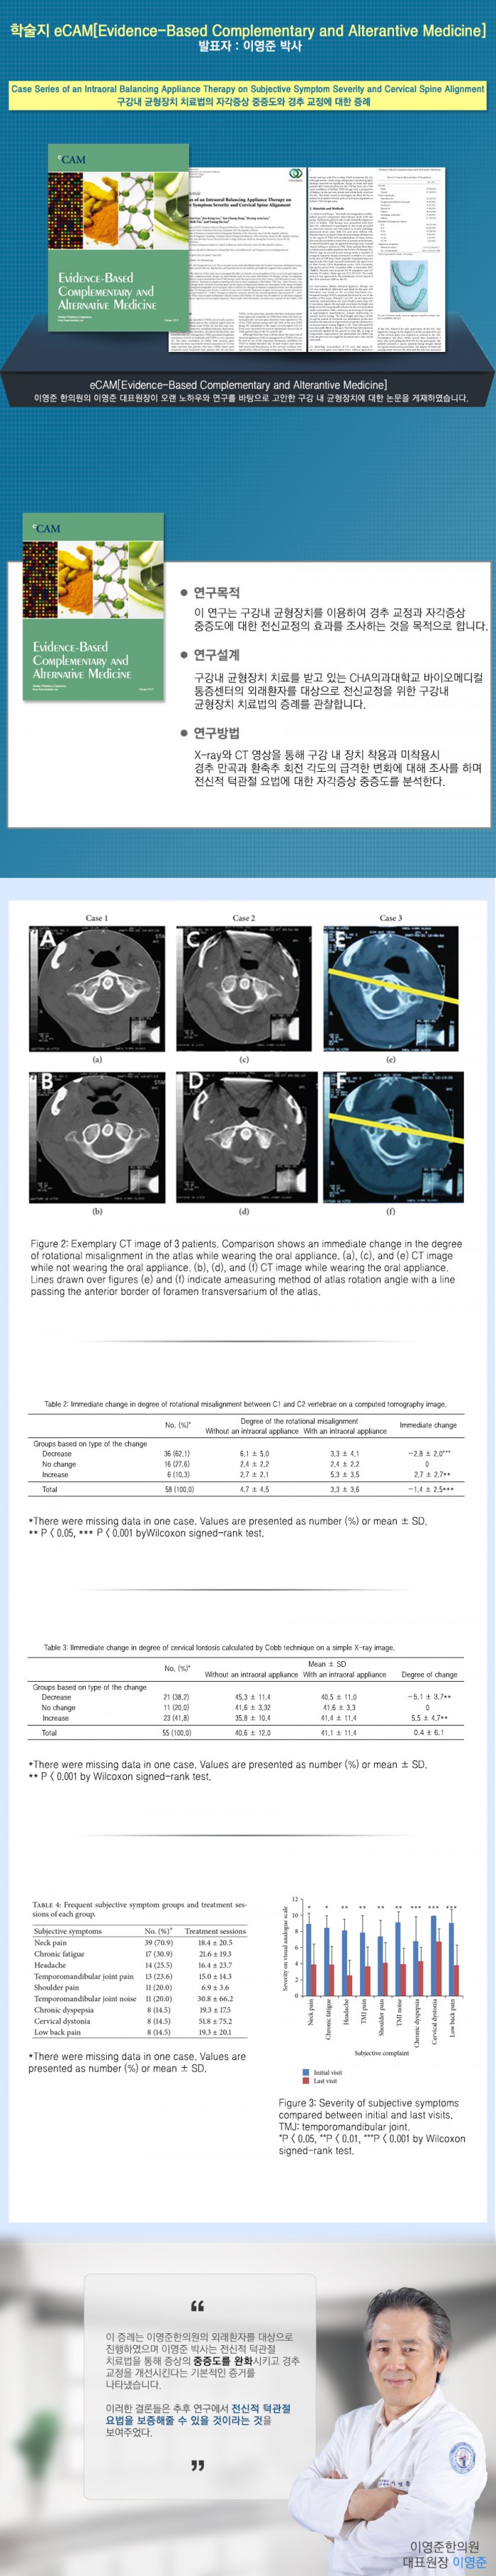

Case Series of an Intraoral Balancing Appliance Therapy on Subjective Symptom Severity and Cervical …

Case Series of an Intraoral Balancing Appliance Therapy on Subjective …